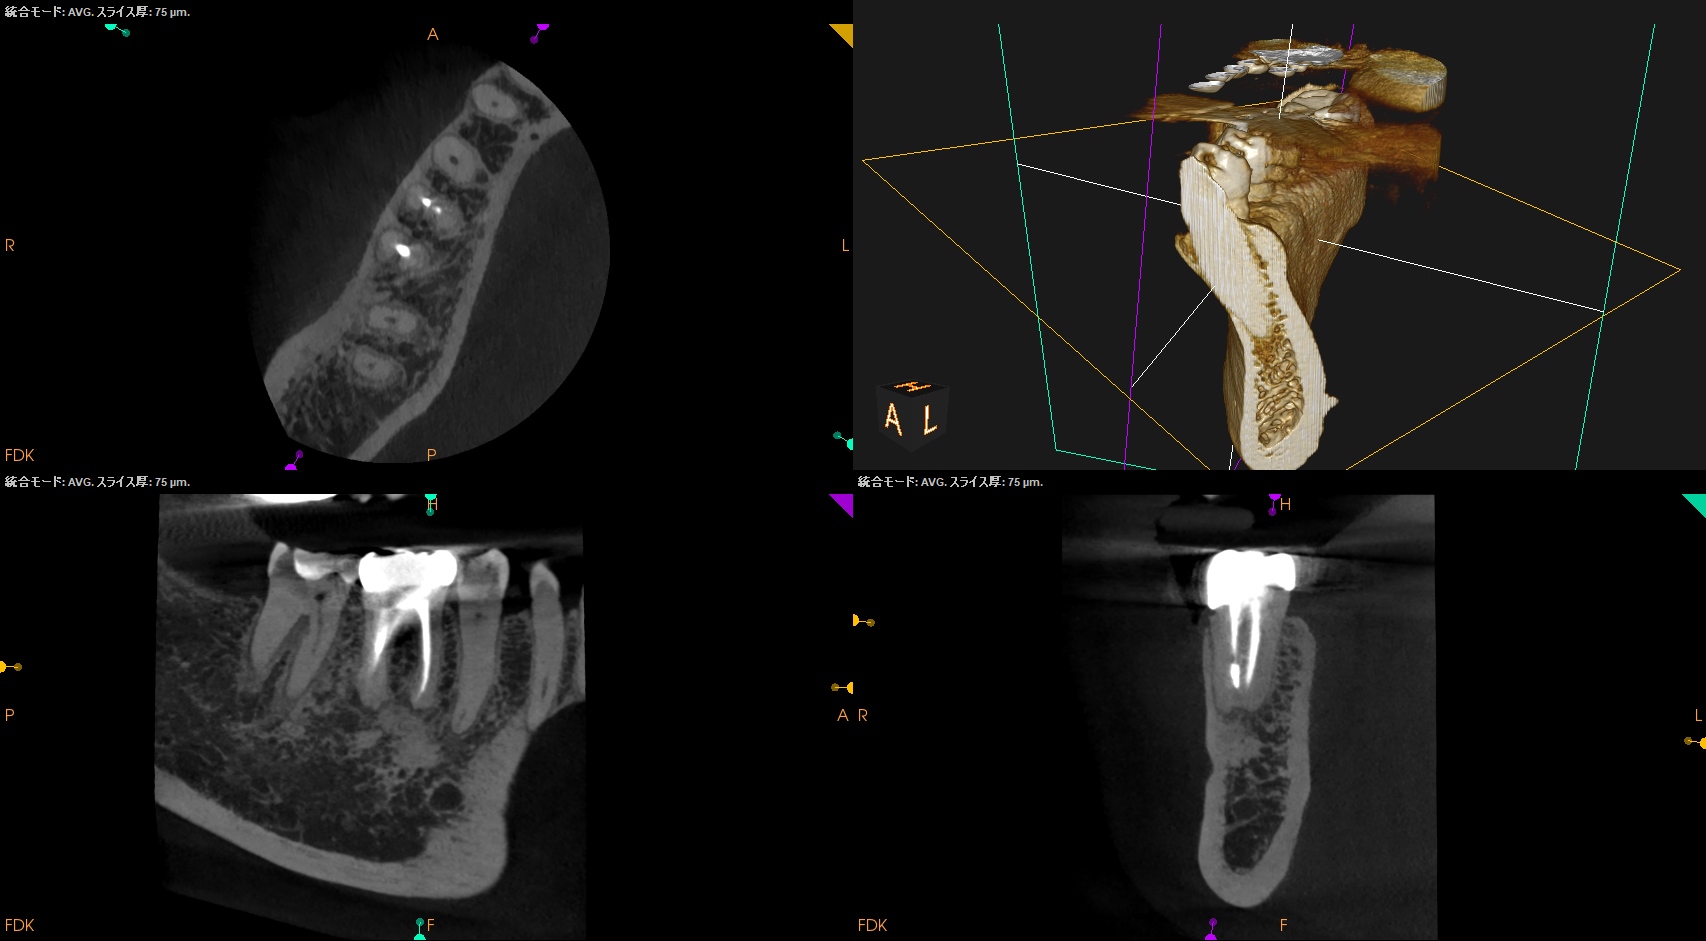

術後にPA, CBCTを撮影した。

MB

ML

D